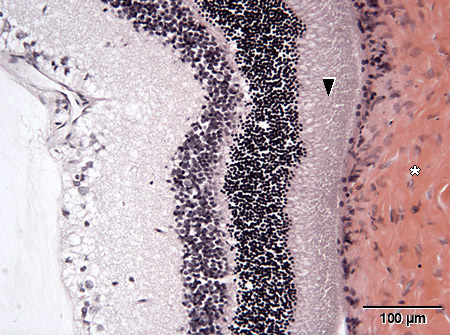

Valomikroskooppikuva rotan silmän verkokalvosta.H&E

tähti = kovakalvo, skleera

nuolenpää = sauva- ja tappisolukerros